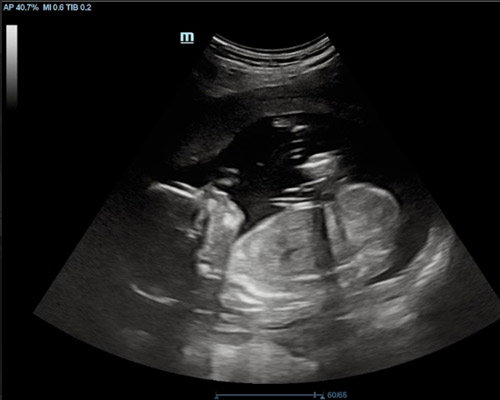

A reassurance scan is an ultrasound carried out during pregnancy to check how your baby is doing and to offer extra peace of mind between routine appointments. Many parents choose this type of scan when they want a closer look at their baby’s progress or simply wish to see them again.

During the scan, the sonographer looks at key signs of development such as heartbeat, movement, overall activity and positioning within the womb. This non-invasive method provides a clear picture of how things are progressing and can help ease common worries.

For many families, a reassurance scan near Worksop becomes a reassuring and memorable experience, especially when they can watch their baby moving on the screen.

- Observe your baby’s movements during the scan

- Visual confirmation of the fetal heartbeat

You may be able to see your baby’s movements, heartbeat, position and general activity during the scan.